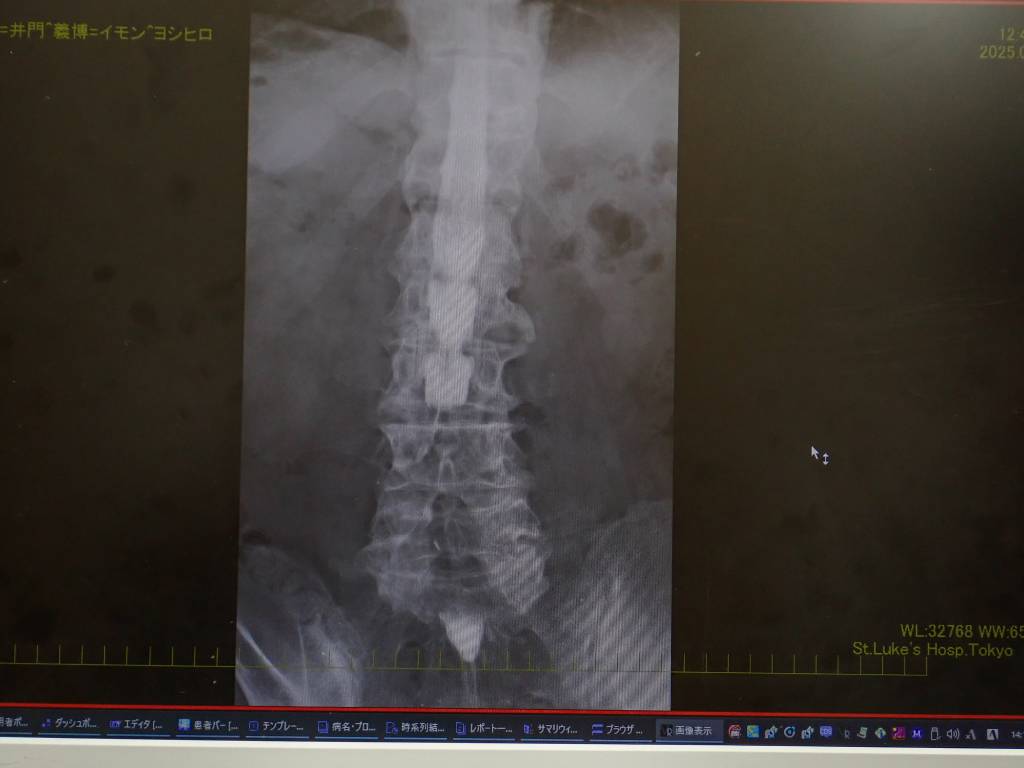

造影剤によるレントゲン写真、白いのが造影剤。

砂時計みたいにくびれている部分があるので造影剤が入っていきません。

横からの図。

要点は1箇所です。